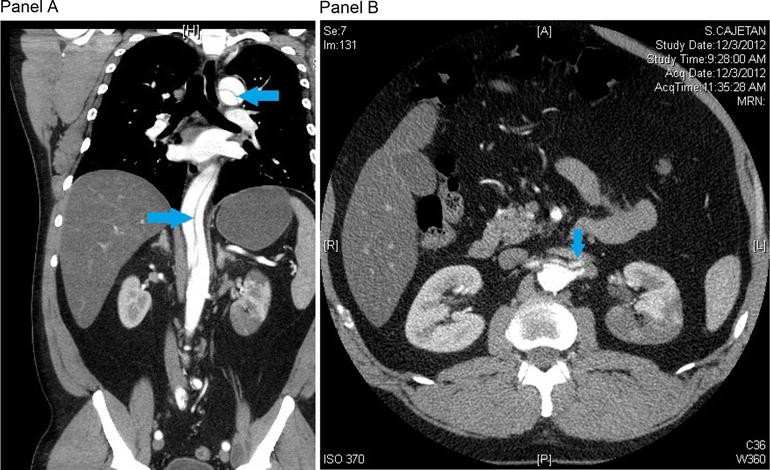

CT angiogram. There is a type B aortic dissection (Panel A, blue arrows) extending from just below the left subclavian artery to the proximal iliac arteries. The left main renal artery arises from the false lumen. A supernumerary left renal artery arises from the true lumen of the aorta and supplies a segment of that kidney (Panel B, blue arrow). The right renal artery is supplied by the true lumen, which is compressed by the false lumen at the site of the right renal artery takeoff

Following multidisciplinary evaluation, consensus was reached that the time for surgical intervention to preserve the left kidney had passed. It was noted that the right kidney appeared to be perfused and the left kidney had a warm ischemic time of approximately 12 h. Given the duration of warm ischemic time and lack of evidence of other limb or visceral malperfusion, surgical intervention was deemed unlikely to be beneficial and intensive medical management was recommended. Medical therapy was selected with careful monitoring of renal function and visceral and extremity perfusion. The infusions of esmolol and nitroprusside were uptitrated and the patient was given hydromorphone and fentanyl for pain. He was intubated for airway protection in the setting of altered mental status and was monitored in the cardiac intensive care unit with goal heart rate <60 beats per minute and goal systolic blood pressure 100–120 mmHg.